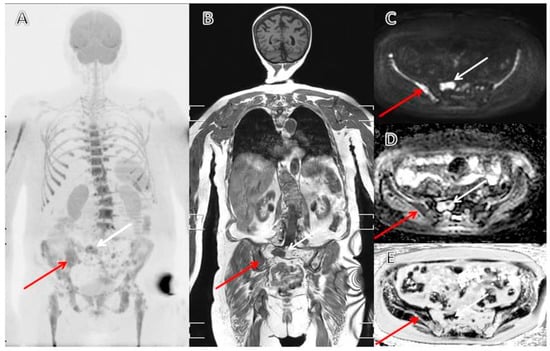

3.4. The Evolving Role of FDG-PET/CT in Multiple Myeloma

- Role of 18 F-FDG PET/CT in the Diagnosis and Management of Multiple Myeloma and Other Plasma Cell Disorders: A Consensus Statement by the International Myeloma Working Group-Clinical Key. Available online: https://www-clinicalkey-com.proxy2-bib.sdu.dk/#!/content/journal/1-s2.0-S1470204517301894 (accessed on 5 March 2020).

- Zamagni, E.; Nanni, C.; Patriarca, F.; Englaro, E.; Castellucci, P.; Geatti, O.; Tosi, P.; Tacchetti, P.; Cangini, D.; Perrone, G.; et al. A prospective comparison of 18F-fluorodeoxyglucose positron emission tomography-computed tomography, magnetic resonance imaging and whole-body planar radiographs in the assessment of bone disease in newly diagnosed multiple myeloma. Haematologica 2007, 92, 50–55. [Google Scholar] [CrossRef] [PubMed]

- Bartel, T.B.; Haessler, J.; Brown, T.L.Y.; Shaughnessy, J.D.; van Rhee, F.; Anaissie, E.; Alpe, T.; Angtuaco, E.; Walker, R.; Epstein, J.; et al. F18-fluorodeoxyglucose positron emission tomography in the context of other imaging techniques and prognostic factors in multiple myeloma. Blood 2009, 114, 2068–2076. [Google Scholar] [CrossRef]

- Zamagni, E.; Patriarca, F.; Nanni, C.; Zannetti, B.; Englaro, E.; Pezzi, A.; Tacchetti, P.; Buttignol, S.; Perrone, G.; Brioli, A.; et al. Prognostic relevance of 18-F FDG PET/CT in newly diagnosed multiple myeloma patients treated with up-front autologous transplantation. Blood 2011, 118, 5989–5995. [Google Scholar] [CrossRef]

- Moreau, P.; Attal, M.; Caillot, D.; Macro, M.; Karlin, L.; Garderet, L.; Facon, T.; Benboubker, L.; Escoffre-Barbe, M.; Stoppa, A.-M.; et al. Prospective Evaluation of Magnetic Resonance Imaging and [18F]Fluorodeoxyglucose Positron Emission Tomography-Computed Tomography at Diagnosis and Before Maintenance Therapy in Symptomatic Patients With Multiple Myeloma Included in the IFM/DFCI 2009 Trial: Results of the IMAJEM Study. J. Clin. Oncol. 2017, 35, 2911–2918. [Google Scholar] [PubMed]

- Pawlyn, C.; Fowkes, L.; Otero, S.; Jones, J.R.; Boyd, K.D.; Davies, F.E.; Morgan, G.J.; Collins, D.J.; Sharma, B.; Riddell, A.; et al. Whole-body diffusion-weighted MRI: A new gold standard for assessing disease burden in patients with multiple myeloma? Leukemia 2016, 30, 1446–1448. [Google Scholar] [CrossRef] [PubMed]